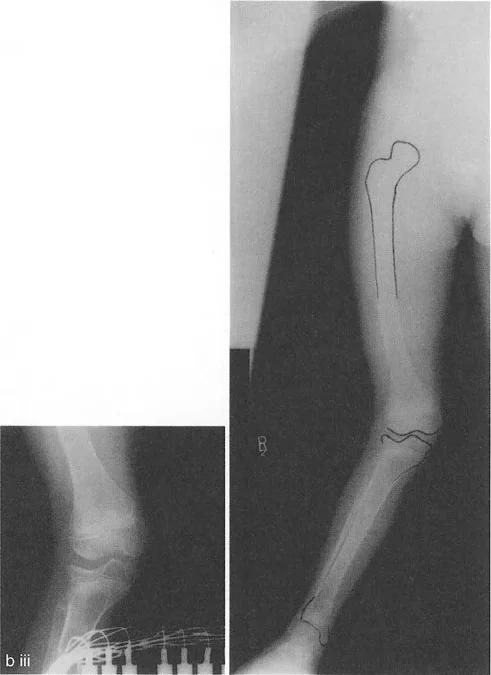

* التئام العظم بعد الصدمة بشكل خاطئ: كسر سالتر-هاريس لدى الأطفال أو كسر بين اللقمتين لدى البالغين يلتئم بشكل سيء ينتج عنه درجة مميزة و/أو سوء توجيه للقم.

* توقف النمو المركزي (تشوه ذيل السمكة): توقف النمو في المركز الدقيق لصفيحة النمو الفخذية البعيدة يتسبب في سوء توجيه اللقمتين وانحدارهما نحو المنتصف، مما يخلق مظهراً كلاسيكياً "لذيل السمكة" على صور الأشعة السينية الأمامية الخلفية.

على سبيل المثال، يبدو سوء توجيه "ذيل السمكة" الدرامي الناتج عن توقف النمو المركزي مخيفاً على الأشعة السينية، ولكنه غالباً لا يتعارض بشكل كبير مع وظيفة المفصل أو استقرار الأربطة أو نطاق الحركة. قد يعاني المريض من انحراف في المحور الميكانيكي، لكن المفصل نفسه يستمر في الحركة بسلاسة.

التأثير الجراحي: بسبب هذا التسامح الهندسي، يمكن غالباً إعادة محاذاة سوء المحاذاة الناتج عن إزاحة لقمة الفخذ الأحادية أو سوء توجيهها باستخدام قطع عظم الفخذ فوق اللقمي خارج المفصل. لا تحتاج دائماً إلى تقسيم اللقم وإجراء عملية داخل المفصل عالية المخاطر. على النقيض من ذلك، فإن عدم الاستقرار الشديد الناتج عن درجات عظم الساق يتطلب دائماً تقريباً قطع عظم حقيقي داخل المفصل (رفع الهضبة) بدلاً من مجرد تصحيح في الميتافيزيس، لمنع التدمير السريع للمفصل.